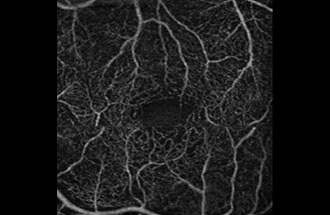

● 光干渉断層血管撮影機器(OCTA)

網膜疾患や緑内障の診断に用いられてきた光干渉断層計(OCT:optical coherence tomography)は、非侵襲的に網膜の断面を描出する機器でとして広く普及しています。当院では、8年前からOCTを導入し、網膜疾患と緑内障の診断と治療に活用してきました。

今回、新たにOCTに血管撮影の機能が付いた光干渉断層血管撮影機器(OCTA: OCT angiography、アンギオOCT)を導入いたしました。

これまで、網膜の血管を描出するには造影剤が必要でした。しかし、この最新の機器を用いることにより、網膜やその下にある脈絡膜血管を、造影剤を用いずに短時間で血管撮影できるようになりました。造影剤を用いた検査(蛍光眼底撮影)は、手間のかかる検査であるだけではなく、副作用のリスクもあるため、実施できない患者様もおられました。 OCTAは、これまでの造影剤を用いた検査の問題点を解決してくれる画期的な機器です。

OCTAを用いることで、これまでの網膜の断層撮影に加えて

② 糖尿病網膜症の早期診断と進展の評価

![]() |

| 糖尿病のない患者さんの 正常眼底 |

糖尿病患者で網膜症なしと 診断された方 |

単純網膜症 |

糖尿病患者さんでは眼底検査で所見がみられない時期にすでに血管の閉塞が始まっていることがわかります。このようにOCTAを用いることで糖尿病網膜症を早期にとらえることが可能です。